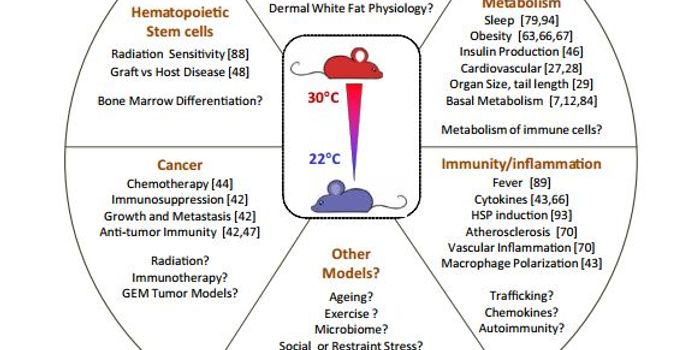

APR 22, 2016Health & MedicineAre mouse research facilities at the right temperature? A recent opinion piece/review published in Trends in Cancer seem ...